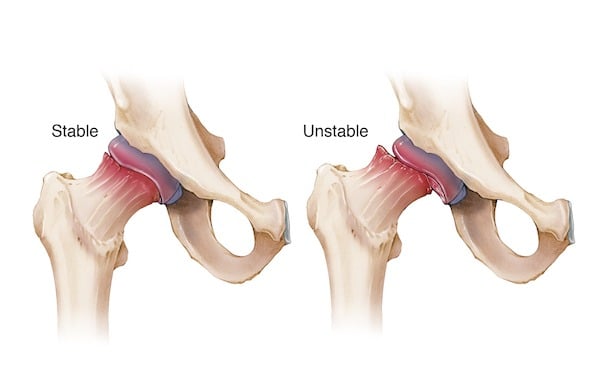

Hip Dysplasia